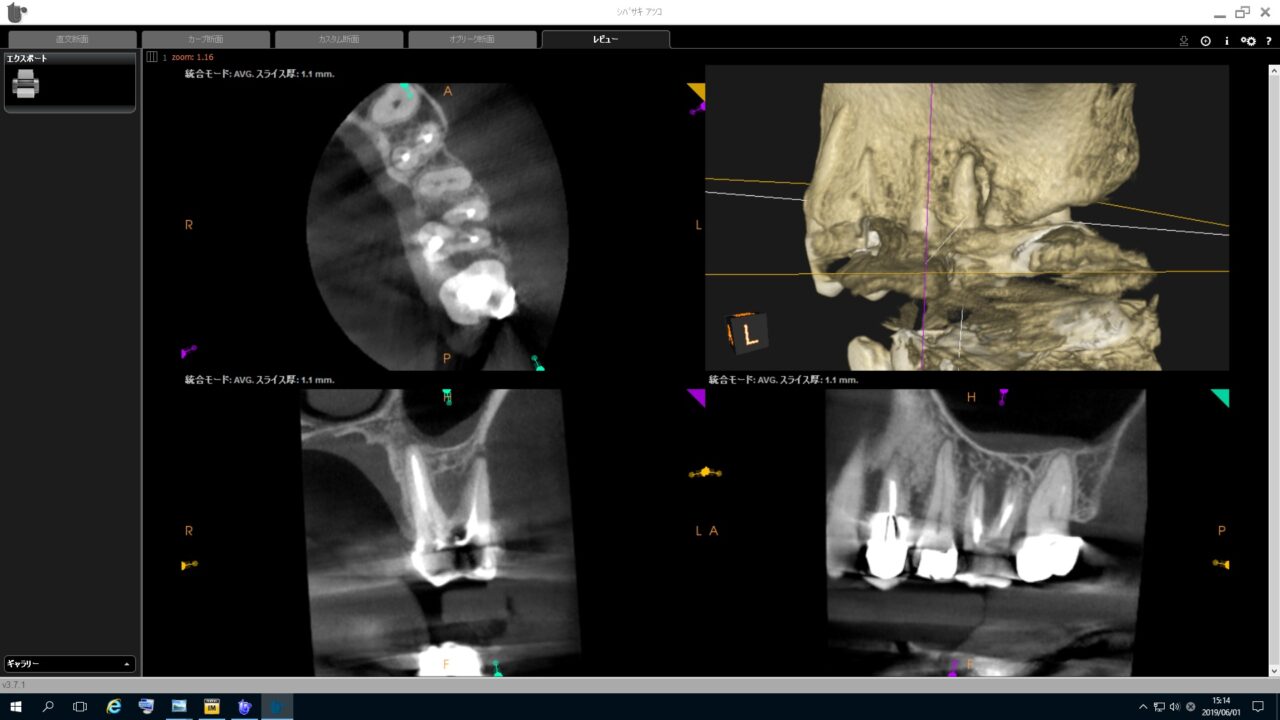

術前のCTより歯根破折を疑われる骨吸収像が確認できます。

術前のレントゲン写真、歯根を取り巻く骨吸収像が確認できます。